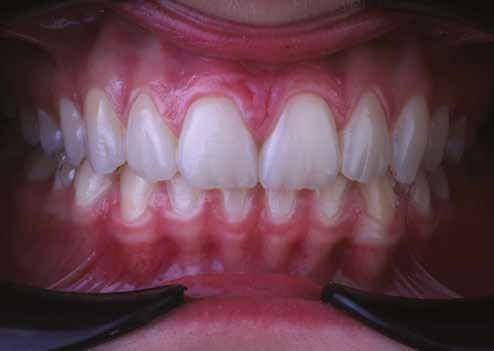

A fogszabályzó kezelések egyik legfontosabb célja, hogy elérjük a lehető legharmonikusabb interokkluzális fogérintkezéseket, továbbá az állcsont relációs helyzetének frontális és szaggitális síkban is megfelelőnek kell lennie. A fogszabályzás befejezésekor a fogpozícióknak nem orthodonciai, hanem protetikai szempontok szerint kell ideálisnak lenniük. Az Invisalign ClinCheck szoftver (Align Technology) segítségével a protetikus az orthodontussal együtt meg tudja határozni azokat a végső fogpozíciókat, amelyek a lehető legjobb végeredmény biztosításához elengedhetetlenek. Bizonyos klinikai paramétereket, mint a fogak klinikai koronájának nagyságát, az egyes fogak fogíven belüli optimális pozícióját, a fogívek egymáshoz viszonyított helyzetét, a fogak között látható rések nagyságát, a frontfogak tengelyének dőlését, az overjet és overbite mértékét már a kezelések megkezdése előtt pontosan definiálni kell. Ezeket az adatokat viszont csak a tervezett végleges fogpótlás ismeretében lehet meghatározni, ezért van szükség az orthodontus és a protetikus szoros együttműködésére.

A rehabilitációs kezeléseknek a célja, hogy a páciensek a lehető leghosszabb időn keresztül képesek legyenek mosolyogni és rágni. A protetikai kezeléseket végző fogorvosoknak helyre kell tudni állítaniuk a fogívek szabályos lefutását és az alsó és felső fogív között megfelelő interokkluzális érintkezéseket kell létrehozniuk. Így lehet csak az ellátás befejezését követően elért végeredmény biológiai szempontokat figyelembe vevő esztétikáját, funkcionális megfelelőségét, hosszú távú fenntarthatóságát biztosítani.

A felnőtt páciensek kezelése során általában egyszerre több ellátásra szoruló elváltozást is diagnosztizálhatunk: hiányzó fogak, kopott fogazat, esetleg régi, nem megfelelő, sérült fogpótlások, rendellenes helyzetben lévő fogak stb… Ezen páciensek kezelésekkel kapcsolatos kérései mindig az esztétikai vagy a rágással kapcsolatos kívánságaik kielégítését szolgálja. A kezelések során a fogorvosoknak nem csak a páciensek kéréseinek teljesítésére, hanem ezzel egyidejűleg a fogazat általános megjelenésének és funkciójának lehetőség szerinti javítására is törekedniük kell. Mindemellett a lehető legtöbb saját foganyag megőrzését és az évek során elvesztett kemény- és lágyrészek pótlását (pl.: hiányzó fogak, sorvadt állcsontgerinc, lágyszöveti defektusok) is szem előtt kell tartaniuk, úgy, hogy közben egy hosszú távon fenntartható eredményekkel járó kezelési tervet állítanak össze. Ezek mindig összetett esetek. Annak érdekében, hogy a fentiekben megfogalmazott összes kezelési célt teljesíteni tudjuk, interdiszciplináris megközelítésre van szükség. Az ilyen komplex rehabilitációs kezeléseket „fogászati megfiatalításnak” nevezzük. Ezeknek a beavatkozásoknak lényege az elhasználódott fogazat biológiai szempontokat figyelembe vevő minimál invazív módon történő helyreállításában rejlik, mely folyamat végére a páciensek fogai visszanyerhetik fiatalkori megjelenésüket.

A fogazat elhasználódása alatt azoknak a degeneratív folyamatoknak az összesített hatását értjük, melyeken az élet során a szervezet keresztülmegy. Ezek lehetnek a fogérintkezések közben fellépő mechanikai erők (abrázió, attríció), endogén vagy exogén eredetű savas közegek által kiváltott kémiai behatások (erózió), kariogén baktériumok által okozott pathológiás folyamatok és parodontális elváltozások, valamint iatrogén ártalmak.